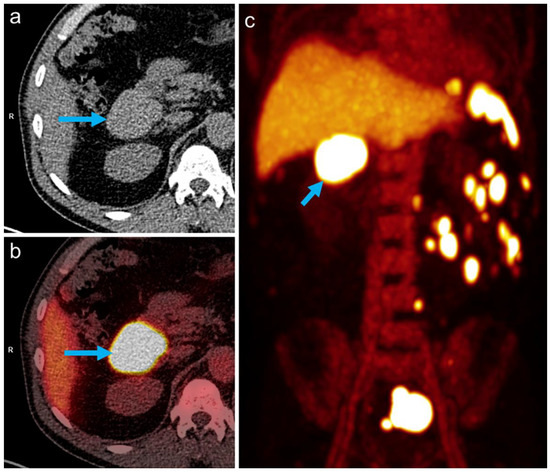

All abdominal and pelvic masses showed a high tracer uptake increasing over time (Figure 2), with the highest uptake values measured in the subhepatic index lesion (Figure 1 and Figure 2, arrows): SUVmean: 69.1/94.1 at 10/25 min after tracer injection, respectively, showing an increase of 36% between the two time points. During the same interval, blood pool activity decreased (SUVmean: 9.6/6.8, −29%), indicating the removal of the labeled, heat-damaged RBCs from the blood by the functioning splenic tissue. The diagnosis of disseminated splenosis was confirmed. Since no symptoms were present and there was no evidence of an increased susceptibility to infections, no further treatment was necessary.

Figure 2. Multiple masses with high tracer uptake seen on RBC-PET/CT (a): non-contrast CT, (b): PET/CT fusion, (c): PET maximum intensity projection (MIP) image acquired 25 min after tracer injection).